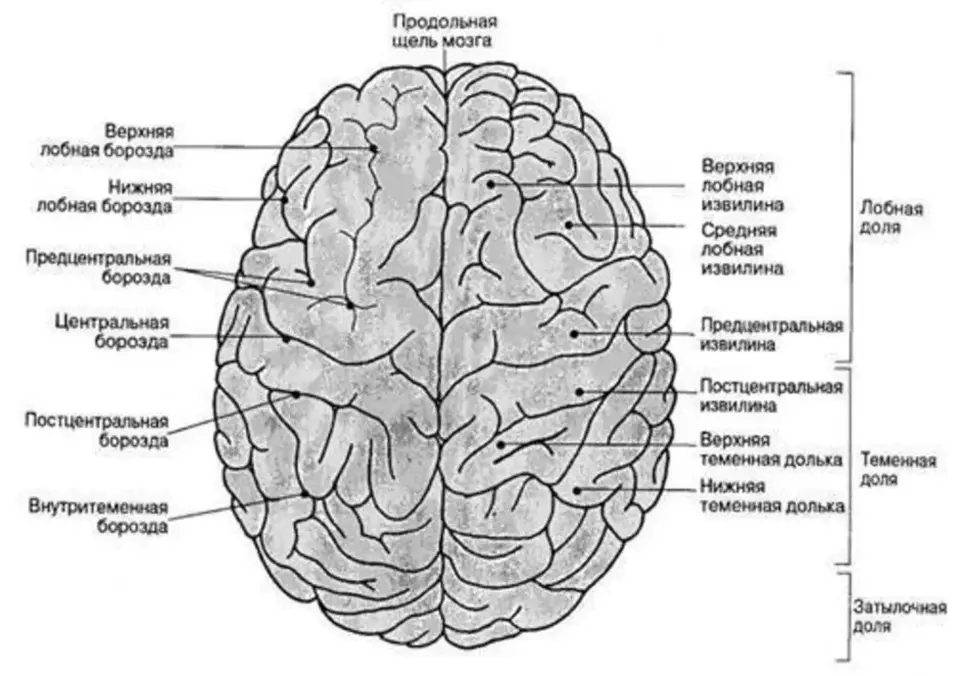

Анатомические снимки верхнелатеральной поверхности головного мозга